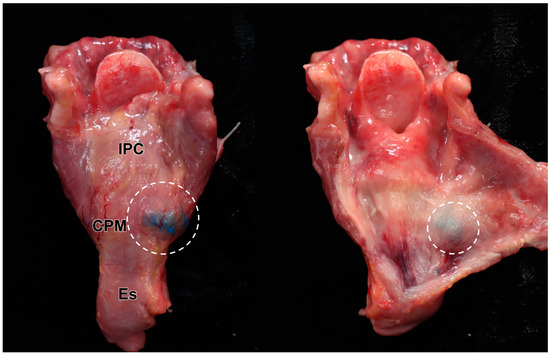

Of the 16 dye injection trials, 12 injections were accurately placed in the targeted CPM (12/16, 75%) (Figure 3). The success rate was not statistically different between the right (5/8, 62.5%) and left (7/8, 87.5%) sides on Fisher’s exact test (p = 0.569). In the four cases where injection into the CPM failed, two cases were identified in the esophagus, one in the prevertebral fascia, and one in the thyroid gland (Table 2). We recorded no case of injected dye diffusing into the inferior constrictor muscle or posterior cricoarytenoid muscle (Figure 4).

The injected dye into the CPM in this study was observed in both lateral and posterolateral areas in 75% of the sides of the CPM, even though only 0.2 mL of the dye was injected. Therefore, a limited volume of BNT injection into the lateral area of the CPM under US guidance is thought to be sufficient for relaxing the CPM. Two mechanisms may account for the injected dye reaching the posterolateral area of the CPM. Rotating the head to the opposite side to be injected may allow exposure of the posterolateral area. In addition, the spread of injected dye along muscle fiber may be another mechanism [16].

The complications of BNT injection, mainly caused by injection at the other structures around the CPM or unexpected spread or diffusion, may come in various forms, including worsening dysphagia or vocal fold paralysis [6,8,9,23]. When considering the anatomical location, the abduction failure of the vocal fold caused by the incorrect injection or spread of BNT into the posterior cricoarytenoid muscles can also occur [12]. There was no case of the injected dye spreading to the intralaryngeal muscles, including the posterior cricoarytenoid muscle [24]. In addition, the injected dye was not found in the inferior constrictor muscle, which can weaken the pharyngeal contraction during swallowing in the presence of BNT [24]. Therefore, US-guided BNT injection with a small volume into the CPM seems to be safe and unlikely to impair the swallowing mechanism, especially in the pharyngeal phase. However, there are two possible complications that can be inferred from the dye found in the thyroid gland in one case. The presence of the dye within the thyroid gland clearly implies that the needle punctured the thyroid gland. Therefore, careful observation is necessary after the procedure to determine the formation of a hematoma [25]. In addition, systemic circulation of BNT can occur, considering the abundance of blood flow in the thyroid gland [26]. The unpredictable complications caused by BNT spread along the esophagus and prevertebral fascia also can occur [26]. Therefore, counseling regarding unexpected and elusive systemic complications, including systemic muscle weakness caused by US-guided BNT injection into the CPM, should be provided to patients before the procedure.

Figure 3. Cadaveric images of the larynx following an ultrasound-guided injection targeting the cricopharyngeus muscle (CPM). Image (A) shows the larynx fully exposed, while image (B) displays the larynx with the thyroid gland (TG), pharynx, and esophagus (Es) retracted to highlight the area where the blue dye was injected into the posterolateral aspect of the CPM. The dye placement within the CPM is clearly visible. The white dotted line in the image (A) indicates the boundary of the cricoid cartilage. CC; cricoid cartilage, IPC; inferior pharyngeal constrictor muscle, TG; thyroid gland (sagittal cut), Tr; trachea, CCA; common carotid artery, Vt; vertebrae.

Figure 4. Results of the US-guided injection: The larynx was detached from the cadaver, and the connective tissue was removed, exposing the blue dye localized solely on the posterolateral side of the cricopharyngeus muscle (CPM) (left image). The dye remained strictly confined within the CPM, with no diffusion into adjacent laryngeal structures (right image). The specimen’s darker appearance is due to formalin fixation and preservation. The white circles indicate the injected dye. IPC; inferior pharyngeal constrictor muscle, Es; esophagus.